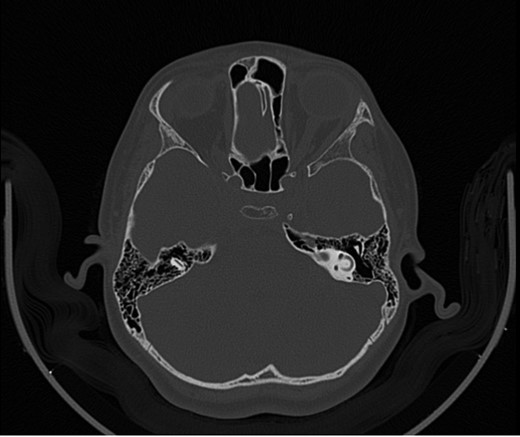

A 14-year-old male patient presented to the ENT clinic with bilateral hearing loss with no other otolaryngological symptoms. History from the patient stated a road traffic accident (RTA) 12 months ago. Meanwhile, the patient had no hearing problems prior to the RTA. Furthermore, detailed history of the accident revealed that the patient had no apparent skull injuries while pure tone audiometry (PTA) on presentation revealed bilateral conductive hearing loss and auditory brainstem response revealed right mild hearing loss and left moderate hearing loss. As a result, he was fitted with hearing aid for four months after presentation and was not compliant to it on the long-term. The patient is a non-smoker and is medically free with normal developmental milestones and negative family history of hearing complaints. Local examination of the ear revealed intact but minimally retracted tympanic membrane bilaterally. PTA was done in 2014 revealed right mild to moderate mixed hearing loss and conductive hearing loss at low frequency (Table 1). Meanwhile, the left ear had mild to moderate sensory hearing loss at high frequency (Table 2). The speech audiogram results show equal canal volume in both ears, less tympanometry pressure on the right ear and less compliance on the right ear (Table 3). The CT showed that both ossicular chains are deranged, and bilateral abnormal ossicles with no fracture or mass (Figures 1–3).

Figure 2:

CT mastoid, deranged right side ossicular disruption.